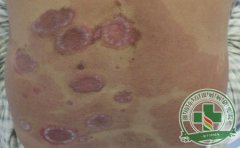

红皮型银屑病治疗须知